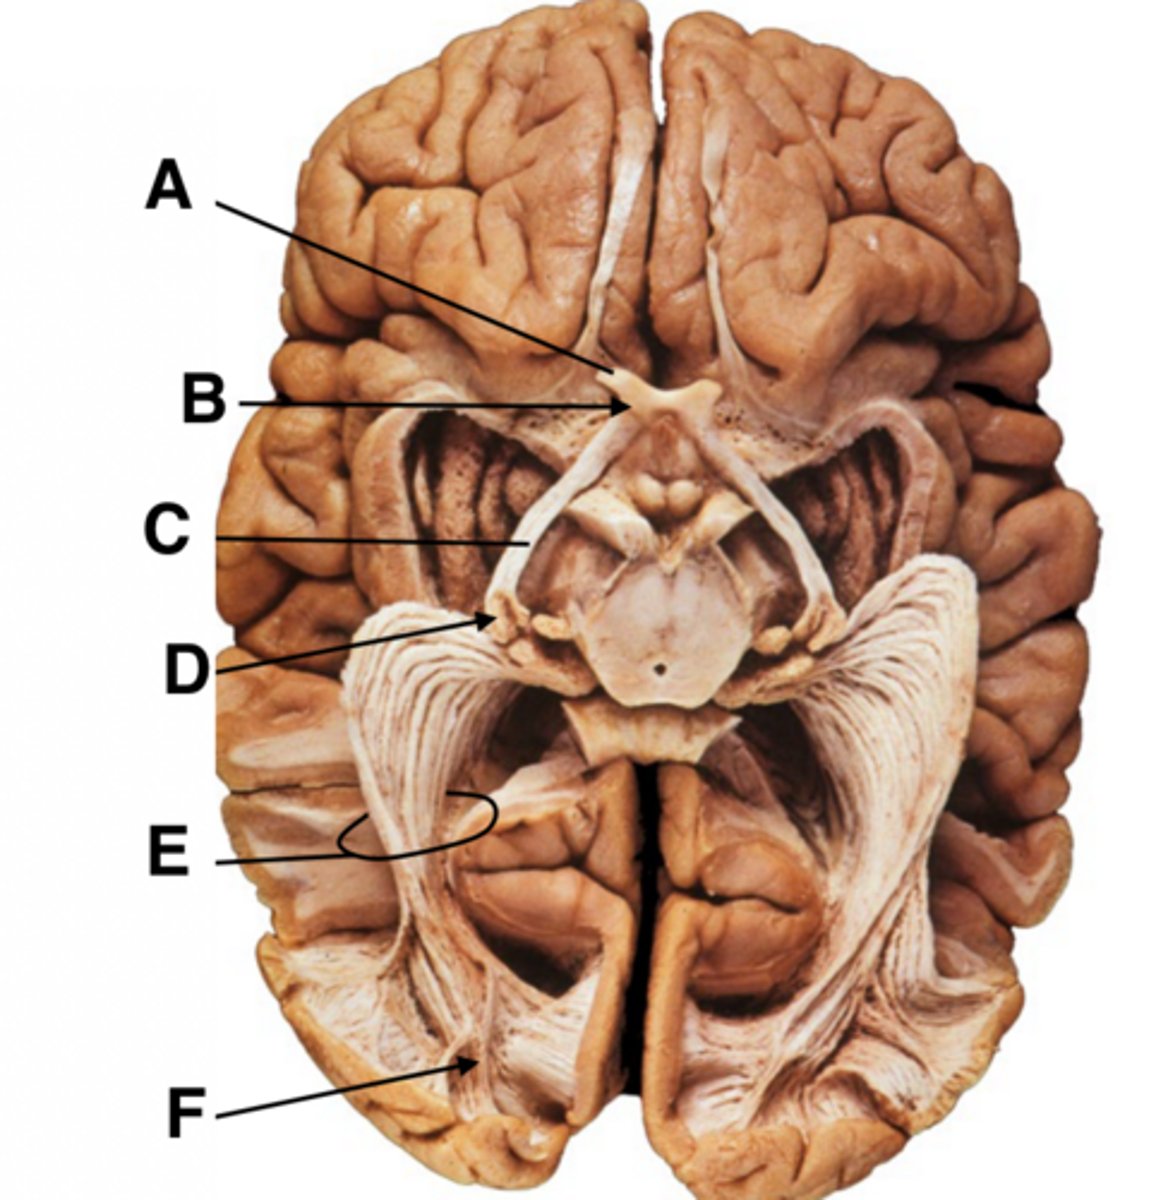

A. Optic nerve

B. Optic chiasm

C. Optic tract

D. Lateral geniculate nucleus (LGN) of thalamus

E. Optic radiation

F. Primary visual cortex